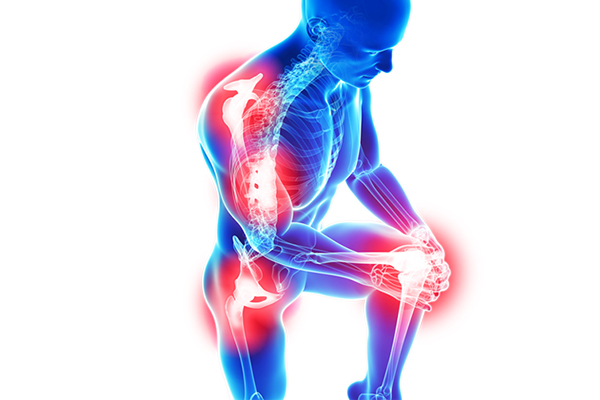

Arithritis

A. Osteoarithitis :

Common degenerative joint disorder Characterised by.

Break down of the Cartilage.

Bony Changes of Joints,. It is usually called as “Wear and Tear arithitis.”

B. Rheumatoid Arthritis :

* Auto immune disorder that is Primarily affects joints.

* It has a Symptom like, warm, Swollen, and Painful joints with restricted movements in joints.